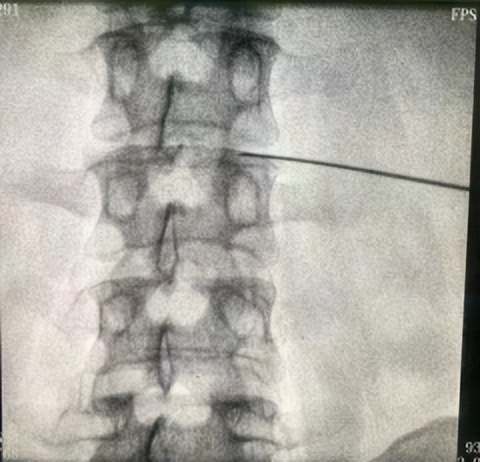

近日,庆城县岐伯中医医院疼痛科在北京海军总医院疼痛诊疗中心张建军主任的指导下成功开展了首例经皮穿刺椎间盘微创射频消融术,填补了我县该项技术的空白。

患者,白某,因间断性腰痛伴左下肢放射性疼痛、左足麻木4年余,先后就诊于西安多家医院,诊断为腰椎间盘突出症,保守治疗未取得满意治疗效果,病情时轻时重,反复发作,影响睡眠及工作,曾有医院建议行开放手术治疗,未接受。近1月上述症状复发且加重,无法正常下地行走,影响日常生活,6月3日患者来我院疼痛科求治,经科室讨论、北京海军总医院疼痛诊疗中心张建军主任会诊决定为患者实施经皮穿刺椎间盘微创射频消融术及臭氧介入治疗术。整个手术过程非常顺利,仅用时15分钟。术后患者即感左下肢放射性疼痛及左足麻木症状消失,当即可下床负重活动,术后第二天查房,患者自诉腰部无疼痛,夜间可正常睡眠,手术后5天康复出院。

经皮穿刺椎间盘微创射频消融术,是由北上广深发达城市疼痛科率先开展的一项治疗技术。主要是在椎间盘突出症患者治疗方法上的创新。椎间盘突出症患者疼痛原始治疗方法有两种,一种是物理康复治疗,比如针灸、中频、蒸汽药浴,另一种是外科开放手术。经皮穿刺椎间盘微创射频消融术是介于两种技术之间,通过影像引导将一根针穿刺至椎间盘的突出部分,通过射频的热凝消融部分椎间盘,减轻突出症状,治疗该疾病。该治疗方法具有效果确切,创伤小,术后当天即可下床活动等优点。